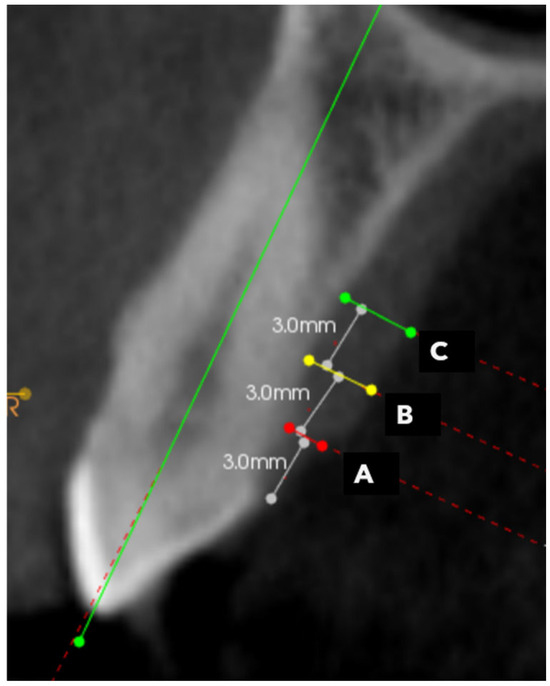

2.3. Radiographic Analysis (CBCT)